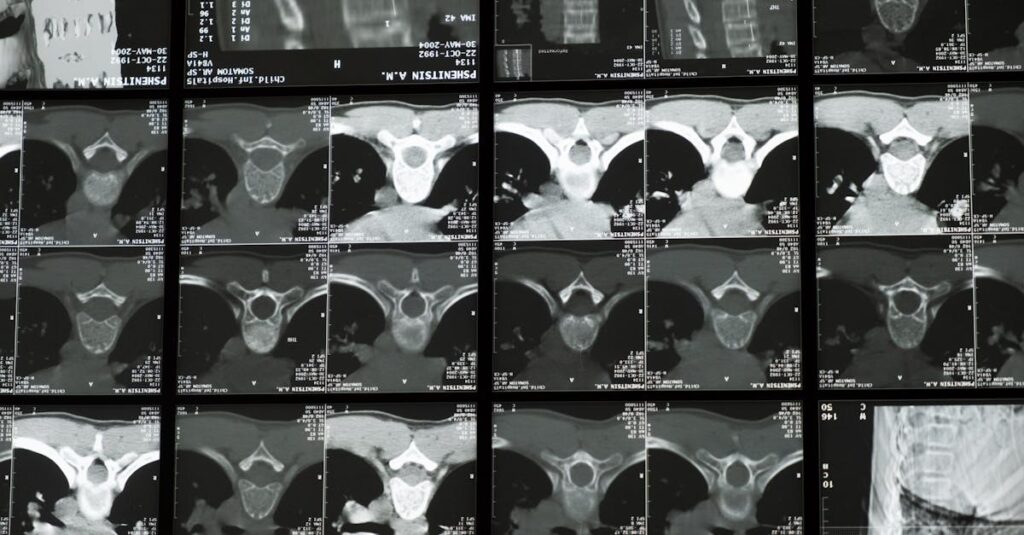

Les tables de décompression, telles que la table SpineMED, intègrent des capteurs qui ajustent automatiquement la force de traction en temps réel. Cela garantit une approche personnalisée, permettant un ciblage précis des zones affectées. Les études montrent que cette méthode offre un soulagement rapide et constate des améliorations significatives de la qualité de vie des patients.

Les dispositifs de décompression, tels que la table SpineMED, permettent d’appliquer une traction douce et contrôlée sur la colonne vertébrale, favorisant ainsi la guérison des disques intervertébraux. Cela aide à réduire la pression sur les nerfs environnants, procurant ainsi un soulagement du mal de dos accompagné d’une amélioration de la mobilité. Les patients témoignent souvent d’une amélioration significative de leur qualité de vie après plusieurs séances de traitement.

Les avancées techniques dans le domaine de la médecine vertebrale, telles que les systèmes de suivi en temps réel, permettent aux professionnels de la santé de surveiller de près les réponses du corps au traitement. Cette capacité à adapter les protocoles en fonction des besoins spécifiques des patients assure une approche personnalisée qui tient compte de l’évolution des symptômes au fil du temps.

Quels examens sont nécessaires avant de commencer un traitement de décompression pour un disque écrasé?

Une IRM ou une radiographie est souvent recommandée pour évaluer l’état de la colonne vertébrale.